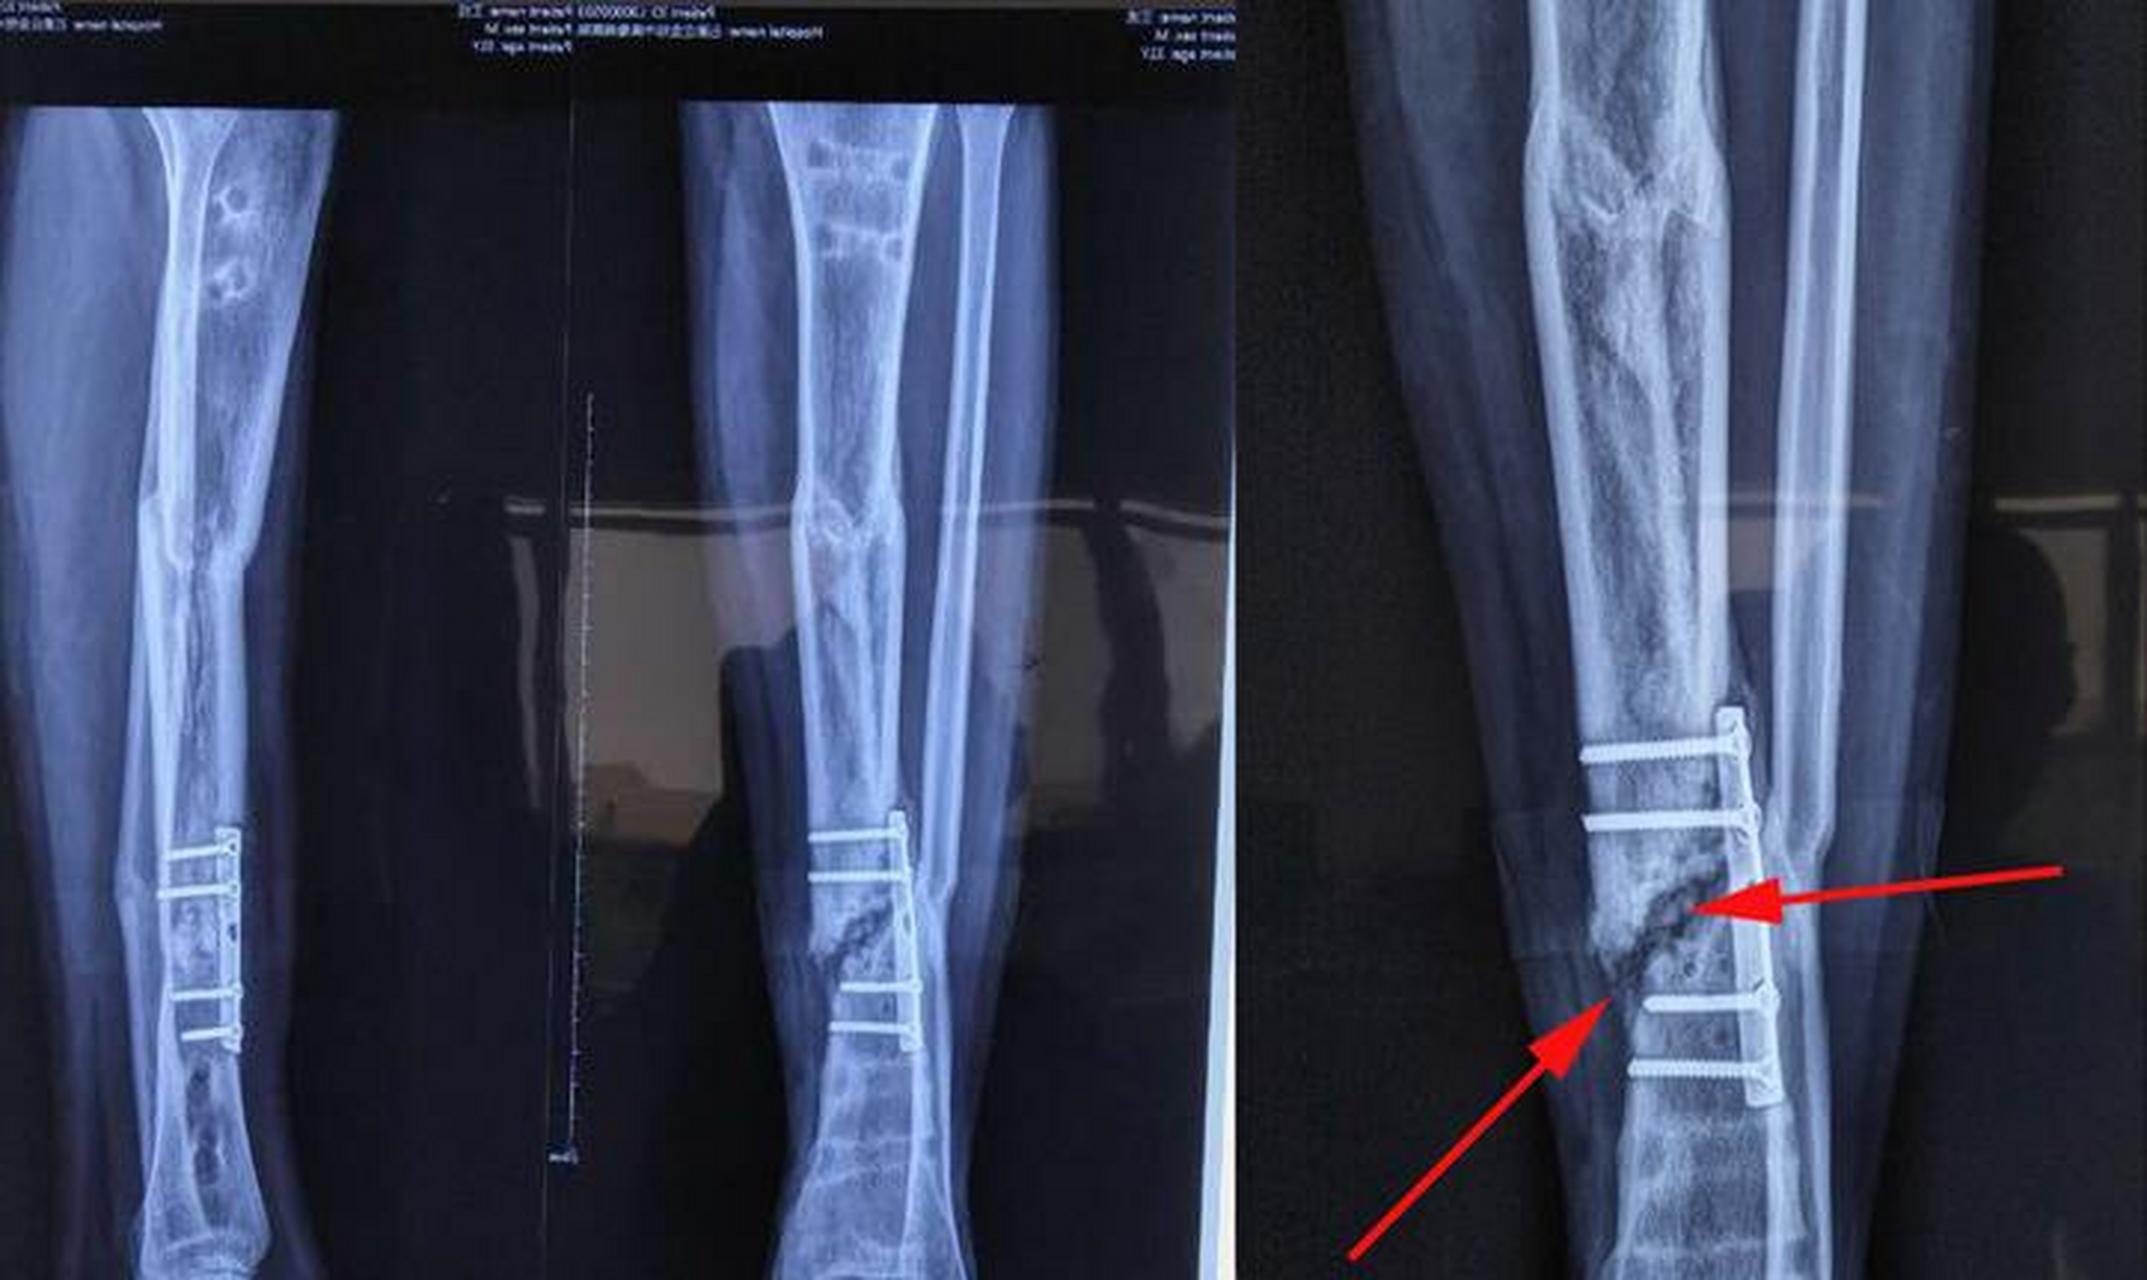

骨折术后半年,复查片[局部愈合不佳]骨折术后半年,复查片[局 - 抖音

闭合复位mipo接骨板技术内固定术,术后一年骨折完全愈合去内固定